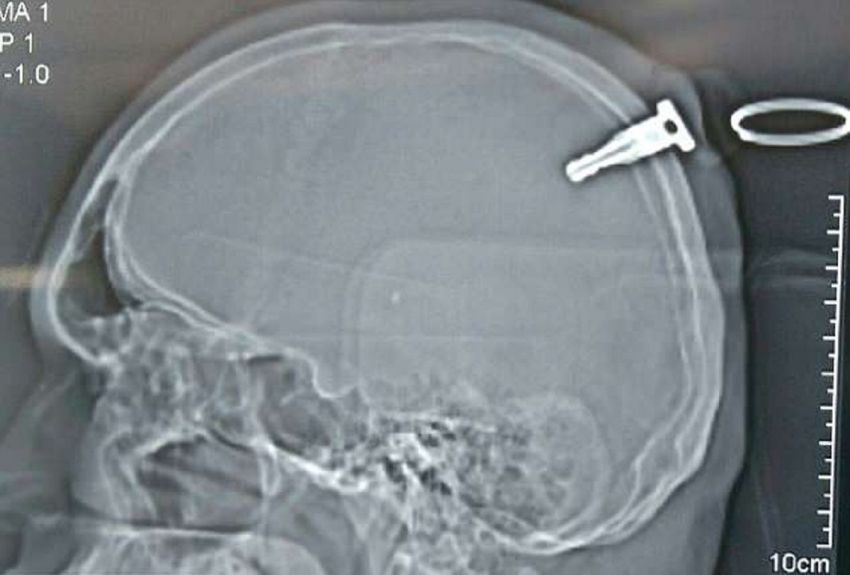

Un joven de 19 años fue operado de urgencia tras terminar con la llave de su motocicleta incrustada en su cráneo, en India. El objeto en cuestión medía 3,8 centímetros de largo y logró ser extraído con éxito, después de realizarse una cirugía atípica.

Según el neurocirujano que lo operó, identificado como Shailendra Uttamrao Markad, el procedimiento que se realizó fue una craneotomía, la cual permitió retirar la llave con éxito, sin lesiones posteriores, publicó el diario británico Daily Mail.